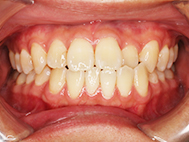

Before

| 症状 | 上下前歯叢生 |

| 治療内容 | 上顎部分裏側矯正 下顎は目立ちにくい透明な装置 |

| 治療期間 | 11ヶ月 |

左上の前歯内側に入っている下の前歯ガチャ歯

左上前歯が下の歯の内側に入っているのが気になるとの事で来院されました。目立たない矯正治療を希望しているとのこでした。 上顎の装置は、歯の裏側(リンガル装置)で下顎は表側で矯正治療を行いました。口を閉じた時、上の前歯が内側に入っている為に下の歯を前に押し出している状態でした。その為、上の歯を前に出すだけではその歯が下とのかみ合わせの関係で、前に飛び出すような治療となってしまいます。 今回の症例ではシュミレーションを見て頂き、下の歯も治療し、内側へ下げることによって上の歯も飛びだすことなく、キレイにおさまることを説明し、上下一緒に矯正することをお勧めさせて頂きました。